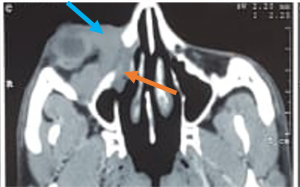

| Sub periosteal abscess[14] | No age/gender predilection | Collection of subperiosteal fluid causing abaxial proptosis along with other signs of cellutlitis | CT- shows hypodense, convex collection with ring enhancement present along orbital wall

| |

Sub Periosteal Abscess. Coronal contrast-enhanced CT image of right orbit showing extraconal marginally enhancing fluid collections located superonasally, consistent with subperiosteal abscess. These are present in continuation with opacified right ethmoidal air cells and right maxillary antrum with soft tissue density with hyperdense content. |